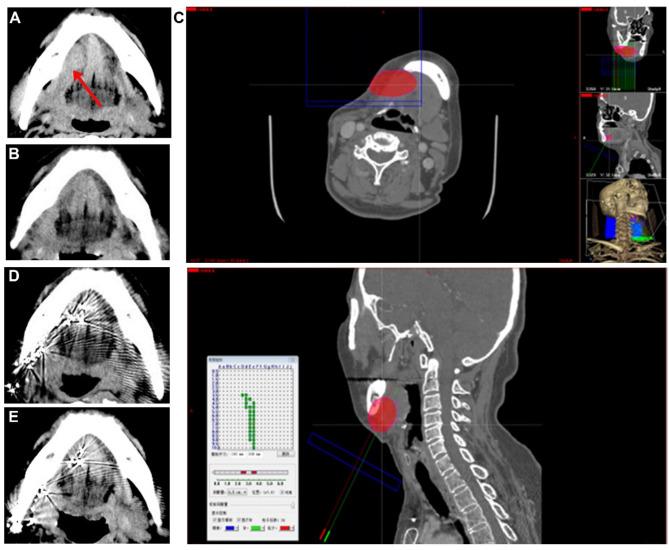

This study reviewed cases of primary malignant sublingual gland tumors, analyzing their characteristics. The treatment methods included surgical excision, with additional radiotherapy, or brachytherapy for advanced stages or positive surgical margins. The study also summarized different treatment approaches, including lymph node dissection and soft tissue reconstruction using free flaps such as the anterolateral thigh flap and forearm flap.

We have gathered 23 cases of sublingual gland malignancies treated at the Department of Oral and Maxillofacial Surgery, School and Hospital of Stomatology, Wuhan University, from January 2013 to May 2024. The most common pathological types were adenoid cystic carcinoma and mucoepidermoid carcinoma, with rare cases of mucosa-associated lymphoid tissue (MALT) lymphoma and nonspecific salivary gland clear cell carcinoma. Early diagnosis and surgical intervention were crucial for a favorable prognosis. Marginal mandibulectomy was necessary for cases involving the mandible. Patients with positive preoperative lymph node detection required cervical lymph node dissection. Extensive tissue defects in the floor of the mouth were effectively reconstructed with free flaps to prevent oral-mandibular fistula.